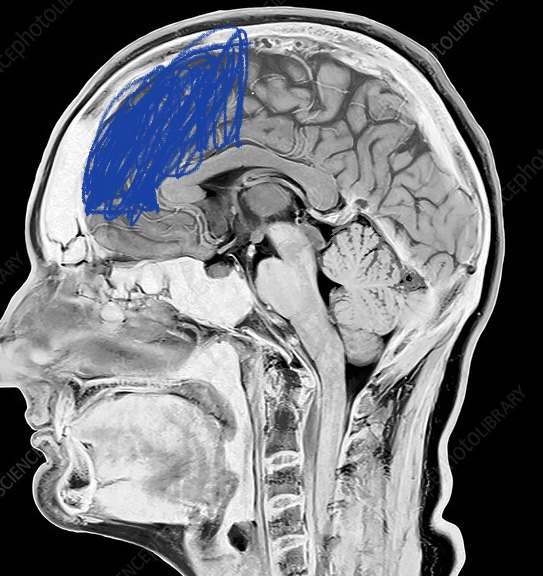

Lack of frontal lobe detected

View attachment 2294576

Negroids have literally have rounding projected foreheads where is this idea of lack of frontal lobe come from, are you talking about there actual brain. I believe they aren’t stupider just intellectually slightly inferior but they make up for it by being socially superior (swagmaxxed basically)